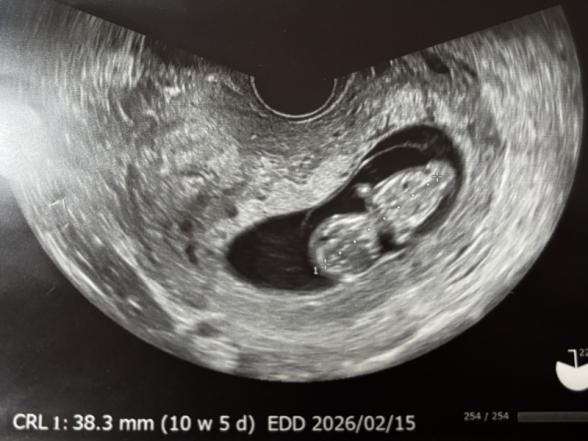

11週〜13週でNTをみると調べたら出てきたのですが、胎児の向きは関係ありますか?もしスルーされたらどうしようと次の検診までドキドキしています。

10w6dのときのエコーではNTは見れないのでしょうか?

また、この向きだと11wすぎてても判別できないのでしょうか?( ; ; )

添付をしてくださったお写真の向きは、赤ちゃんを背中側から見ているものになります。

なのでこのお写真ではNTはわからない角度になります。

エコーを見る時の角度を変えてみることで、真横を向いている赤ちゃんの様子も確認ができるかと思います。